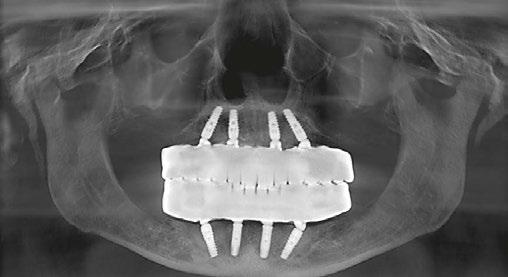

The patient returns four months later for a clinical follow-up (Figures 12A and 12B) and X-rays (Figure 13).

The permanent dentures are then placed over a titanium frame processed by Panthera Dental and stratified in composite at the denture laboratory (Figures 14A-14C).

Figures 12A and 12B: Clinical postoperative situation after 4 months Figure 13: Postoperative X-ray follow-up after 4 months Figures 14A-14C: Permanent denture (14A and 14B), intraoral view (14C)